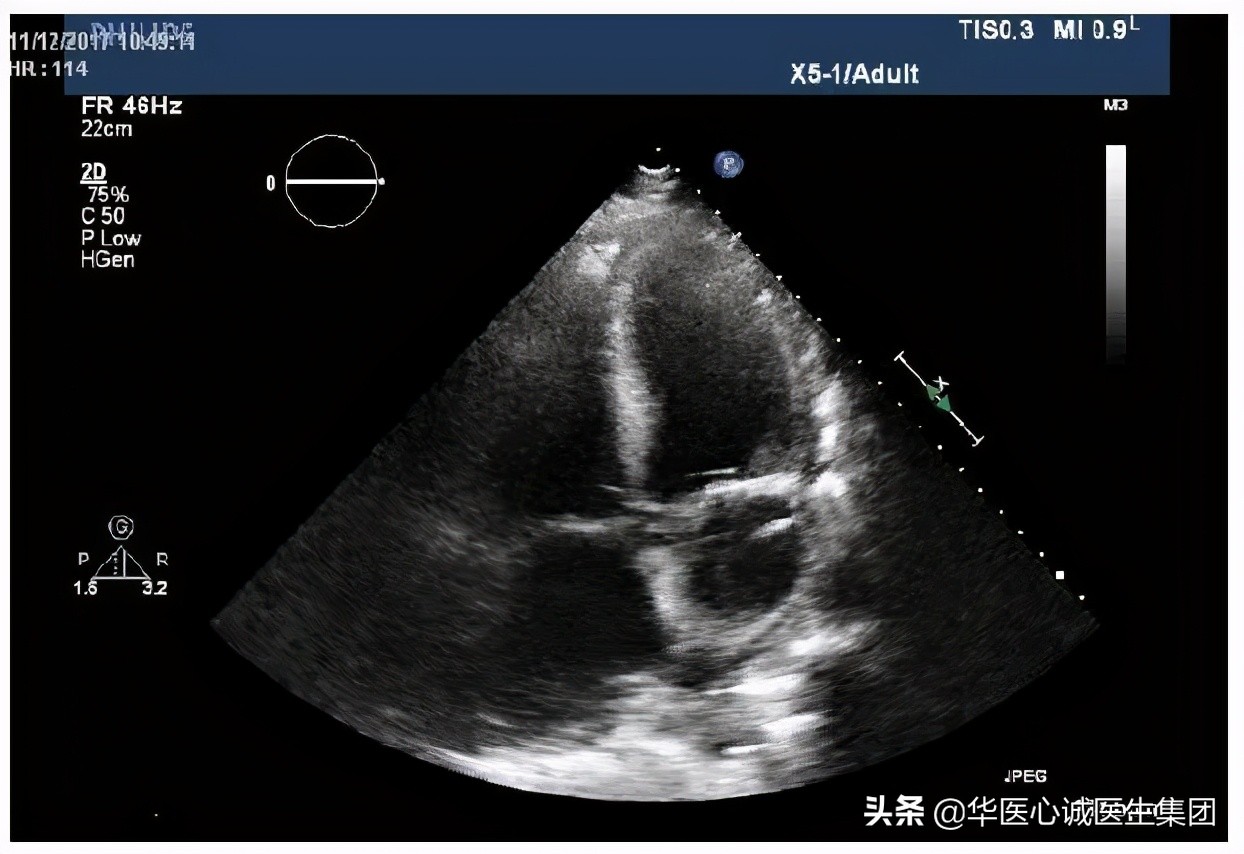

房间隔缺损

该患者还存在房间隔缺损,但缺损面积不大。如果没有其他问题,该患者可能不会出现症状。

但因为有高血压、左心衰、左室肥厚等,左室压力升高后,左房压升高,是否会造成分流量更大?由此可以看出,超声可以清晰的显示病理生理的改变、血流动力学的异常等,这就是超声的魅力所在。

该患者房缺面积不大,但因为左房压高,导致房缺的分流量很大,所以右心明显扩大。